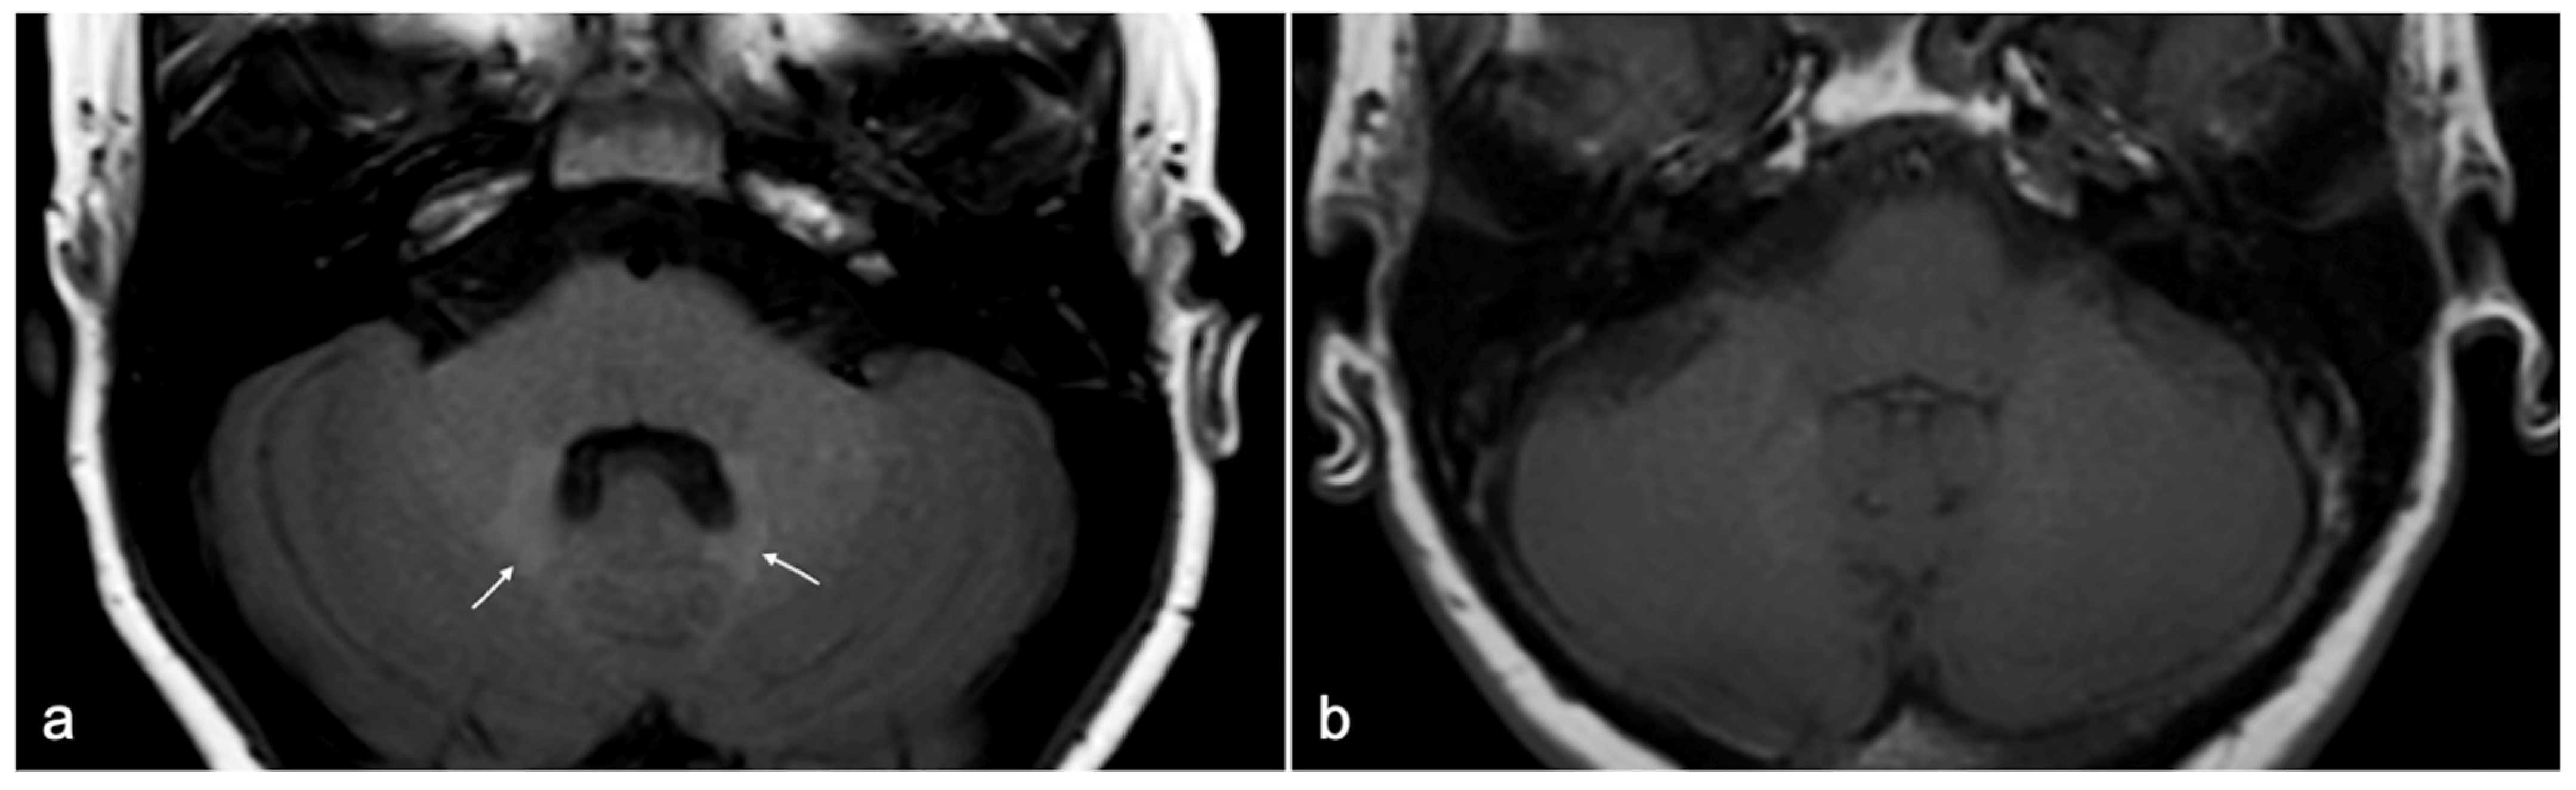

- Kanda, T.; Nakai, Y.; Oba, H.; Toyoda, K.; Kitajima, K.; Furui, S. Gadolinium deposition in the brain. Magn. Reson. Imaging 2016, 34, 1346–1350. [Google Scholar] [CrossRef] [PubMed]

- McDonald, R.J.; McDonald, J.S.; Kallmes, D.F.; Jentoft, M.E.; Murray, D.L.; Thielen, K.R.; Williamson, E.E.; Eckel, L.J. Intracranial Gadolinium Deposition after Contrast-enhanced MR Imaging. Radiology 2015, 275, 772–782. [Google Scholar] [CrossRef] [PubMed]

- Gulani, V.; Calamante, F.; Shellock, F.G.; Kanal, E.; Reeder, S.B. Gadolinium deposition in the brain: Summary of evidence and recommendations. Lancet Neurol. 2017, 16, 564–570. [Google Scholar] [CrossRef]

- Cocozza, S.; Pontillo, G.; Lanzillo, R.; Russo, C.; Petracca, M.; Di Stasi, M.; Paolella, C.; Vola, E.A.; Criscuolo, C.; Moccia, M.; et al. MRI features suggestive of gadolinium retention do not correlate with Expanded Disability Status Scale worsening in Multiple Sclerosis. Neuroradiology 2019, 61, 155–162. [Google Scholar] [CrossRef]

- Scaravilli, A.; Tranfa, M.; Pontillo, G.; Falco, F.; Criscuolo, C.; Moccia, M.; Monti, S.; Lanzillo, R.; Brescia Morra, V.; Palma, G.; et al. MR Imaging Signs of Gadolinium Retention Are Not Associated with Long-Term Motor and Cognitive Outcomes in Multiple Sclerosis. Am. J. Neuroradiol. 2023, 44, 396–402. [Google Scholar] [CrossRef] [PubMed]